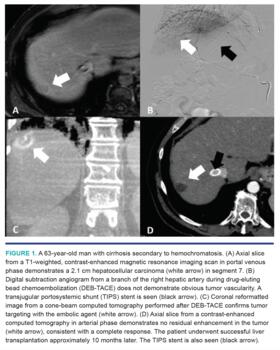

At our institution, we use DEB-TACE as our therapy of choice for bridging and downstaging (Table 1), as this technique has similar efficacy and less toxicity than cTACE.26,27 DEB-TACE can be performed with a variety of bead sizes and chemotherapy combinations. We prefer using a single drug, doxorubicin, since there is no clear advantage to a triple-drug regimen (Figure 1).37 The beads are bound with 50-100 mg of doxorubicin, depending on the patient’s tumor burden. Regarding bead size, DEB-TACE is typically performed using 40-300 μm beads. The most commonly used beads in our practice are Oncozene (Varian) and LC Beads (Boston Scientific). Smaller bead sizes theoretically penetrate deeper into the tumor, but may come with an increased risk of biliary necrosis.38,39 A recent study from our institution demonstrated the safety and efficacy of using as small as 75 μm for DEB-TACE in unresectable HCC.40 Currently, our practice is to use 75 μm beads for selective (ie, sublobar) embolization while reserving larger beads (ie, 100-300 μm beads) for lobar therapies.